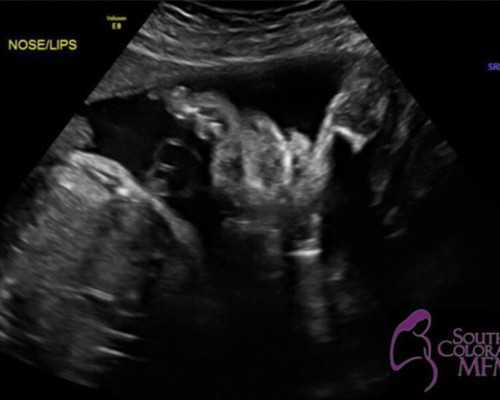

经过近年来医疗技术的发展,我相信我们对试管受精技术的了解越来越多,越来越多的人使用它。试管受精的原理是取出双方的和卵子,然后在体外受精,通过相关技术将受精卵培养成胚胎,最后移植到内。体外受精最大的优点是:通过形态标准筛选高质量的胚胎移植,可......